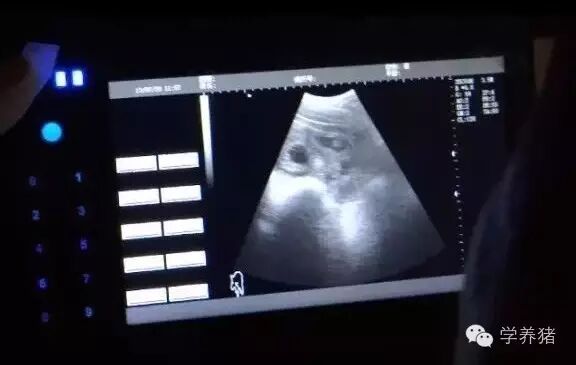

②用妊娠测定仪测定配种后25-30天的母猪,准确率高达98%-100%。